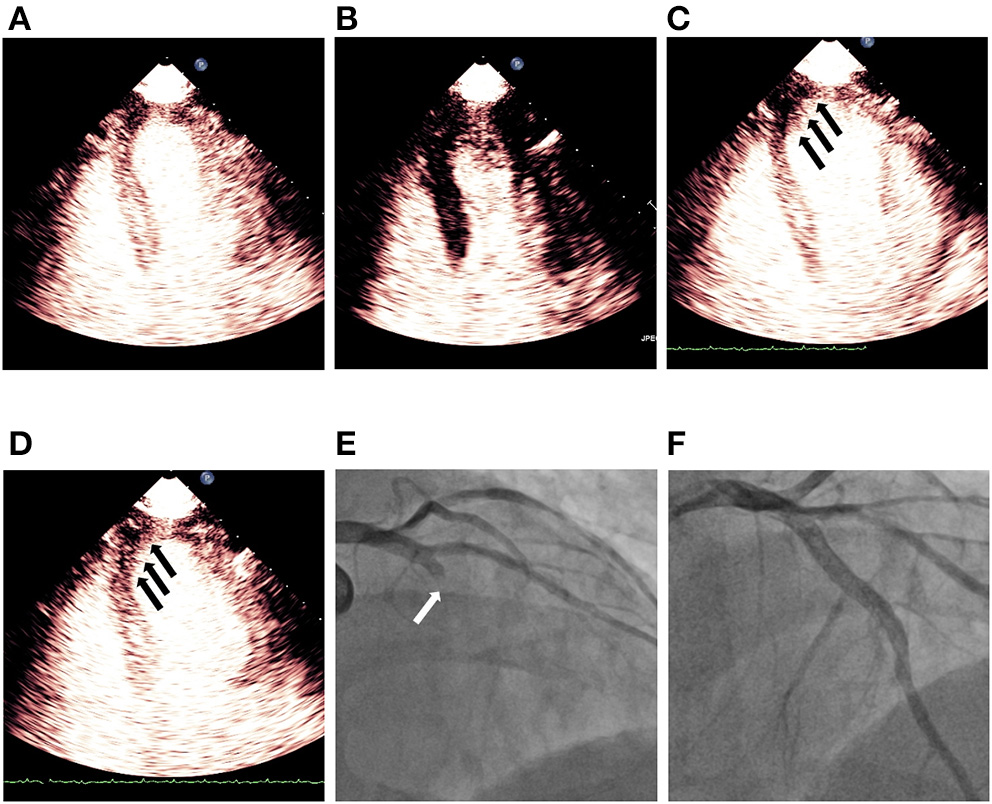

Figure 3

Demonstration of persistent no reflow phenomenon noticed on MCE after successful revascularization of LAD STEMI. (A) Shows myocardial contrast replenishment before the high MI impulse, while (B) indicates complete microbubble destruction immediately after the high MI impulse. (C) Shows a defect (black arrows) in the segments of the infarct zone during replenishment (~4 beats post-high MI impulse), while (D) indicates a persistent defect (black arrows) in LAD territory although a plateau intensity (~10 beats after the high MI impulse) had been reached. (E) Shows blocked LAD (white arrow) before PCI and (F) indicates revascularization of LAD after successful PCI. LAD, left anterior descending; MCE, myocardial contrast echocardiography; PCI, percutaneous coronary intervention; STEMI, ST segment elevated myocardial infarction.